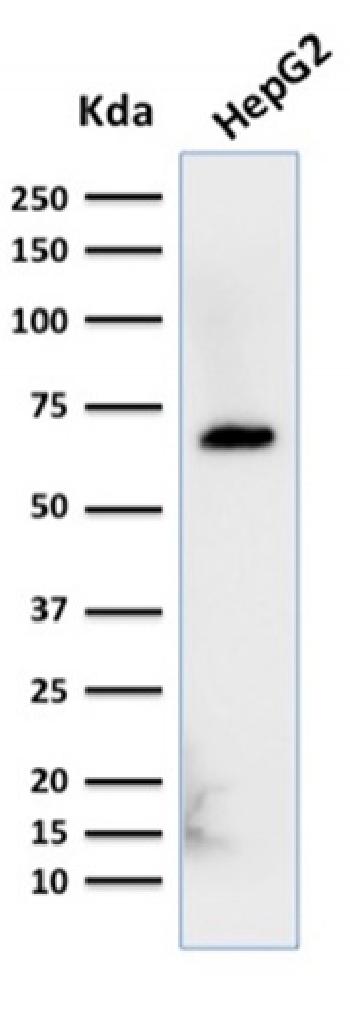

Anti-MRP3 (Multidrµg Resistance-Associated Protein 3) Monoclonal Antibody(Clone: ABCC3/2971)

Fig. 1: Formalin-fixed, paraffin-embedded human Pancreatic Carcinoma stained with MRP3 Mouse Monoclonal Antibody (ABCC3/2971).

| Immunogen Information : | Recombinant fragment (around aa 815-957) of human MRP3 (ABCC3) protein (exact sequence is proprietary) |